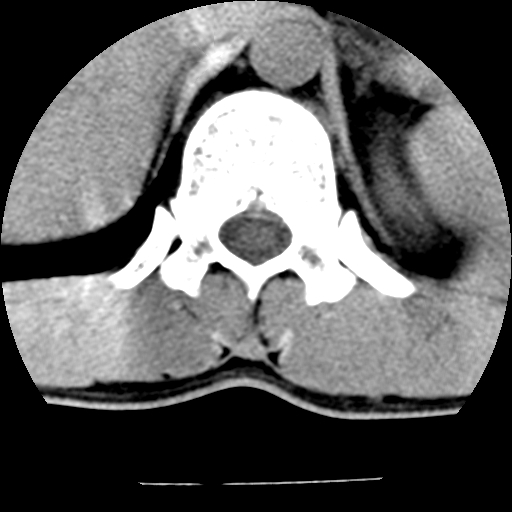

标题: CT10387:男,31岁,胸腰段CT [打印本页]

标题: CT10387:男,31岁,胸腰段CT

男,31岁,从6米高处坠落伤两天,腰背部疼痛,临床要求ct扫描胸10-腰1。请大家帮忙看看骨质有问题吗?

t12、l1锥体前缘轻度楔形变,平扫示椎体前缘骨小梁欠规整,第9幅图示椎体前缘骨质不连续,结合外伤史考虑椎体轻度压缩骨折。

楼主扫描层厚可能较大,每个椎体只有三个层面.

从所示层面分析,无明确骨折征象,象类似病人我个人会建议mri除外骨挫伤.

从上查骨窗第九片椎体前缘皮质显示断裂.压缩骨折?